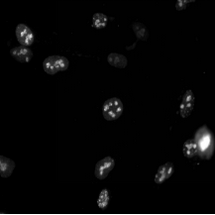

1、細(xì)胞生物學(xué):用于觀察細(xì)胞結(jié)構(gòu)、動態(tài)和相互作用。

03場景圖/實拍效果圖